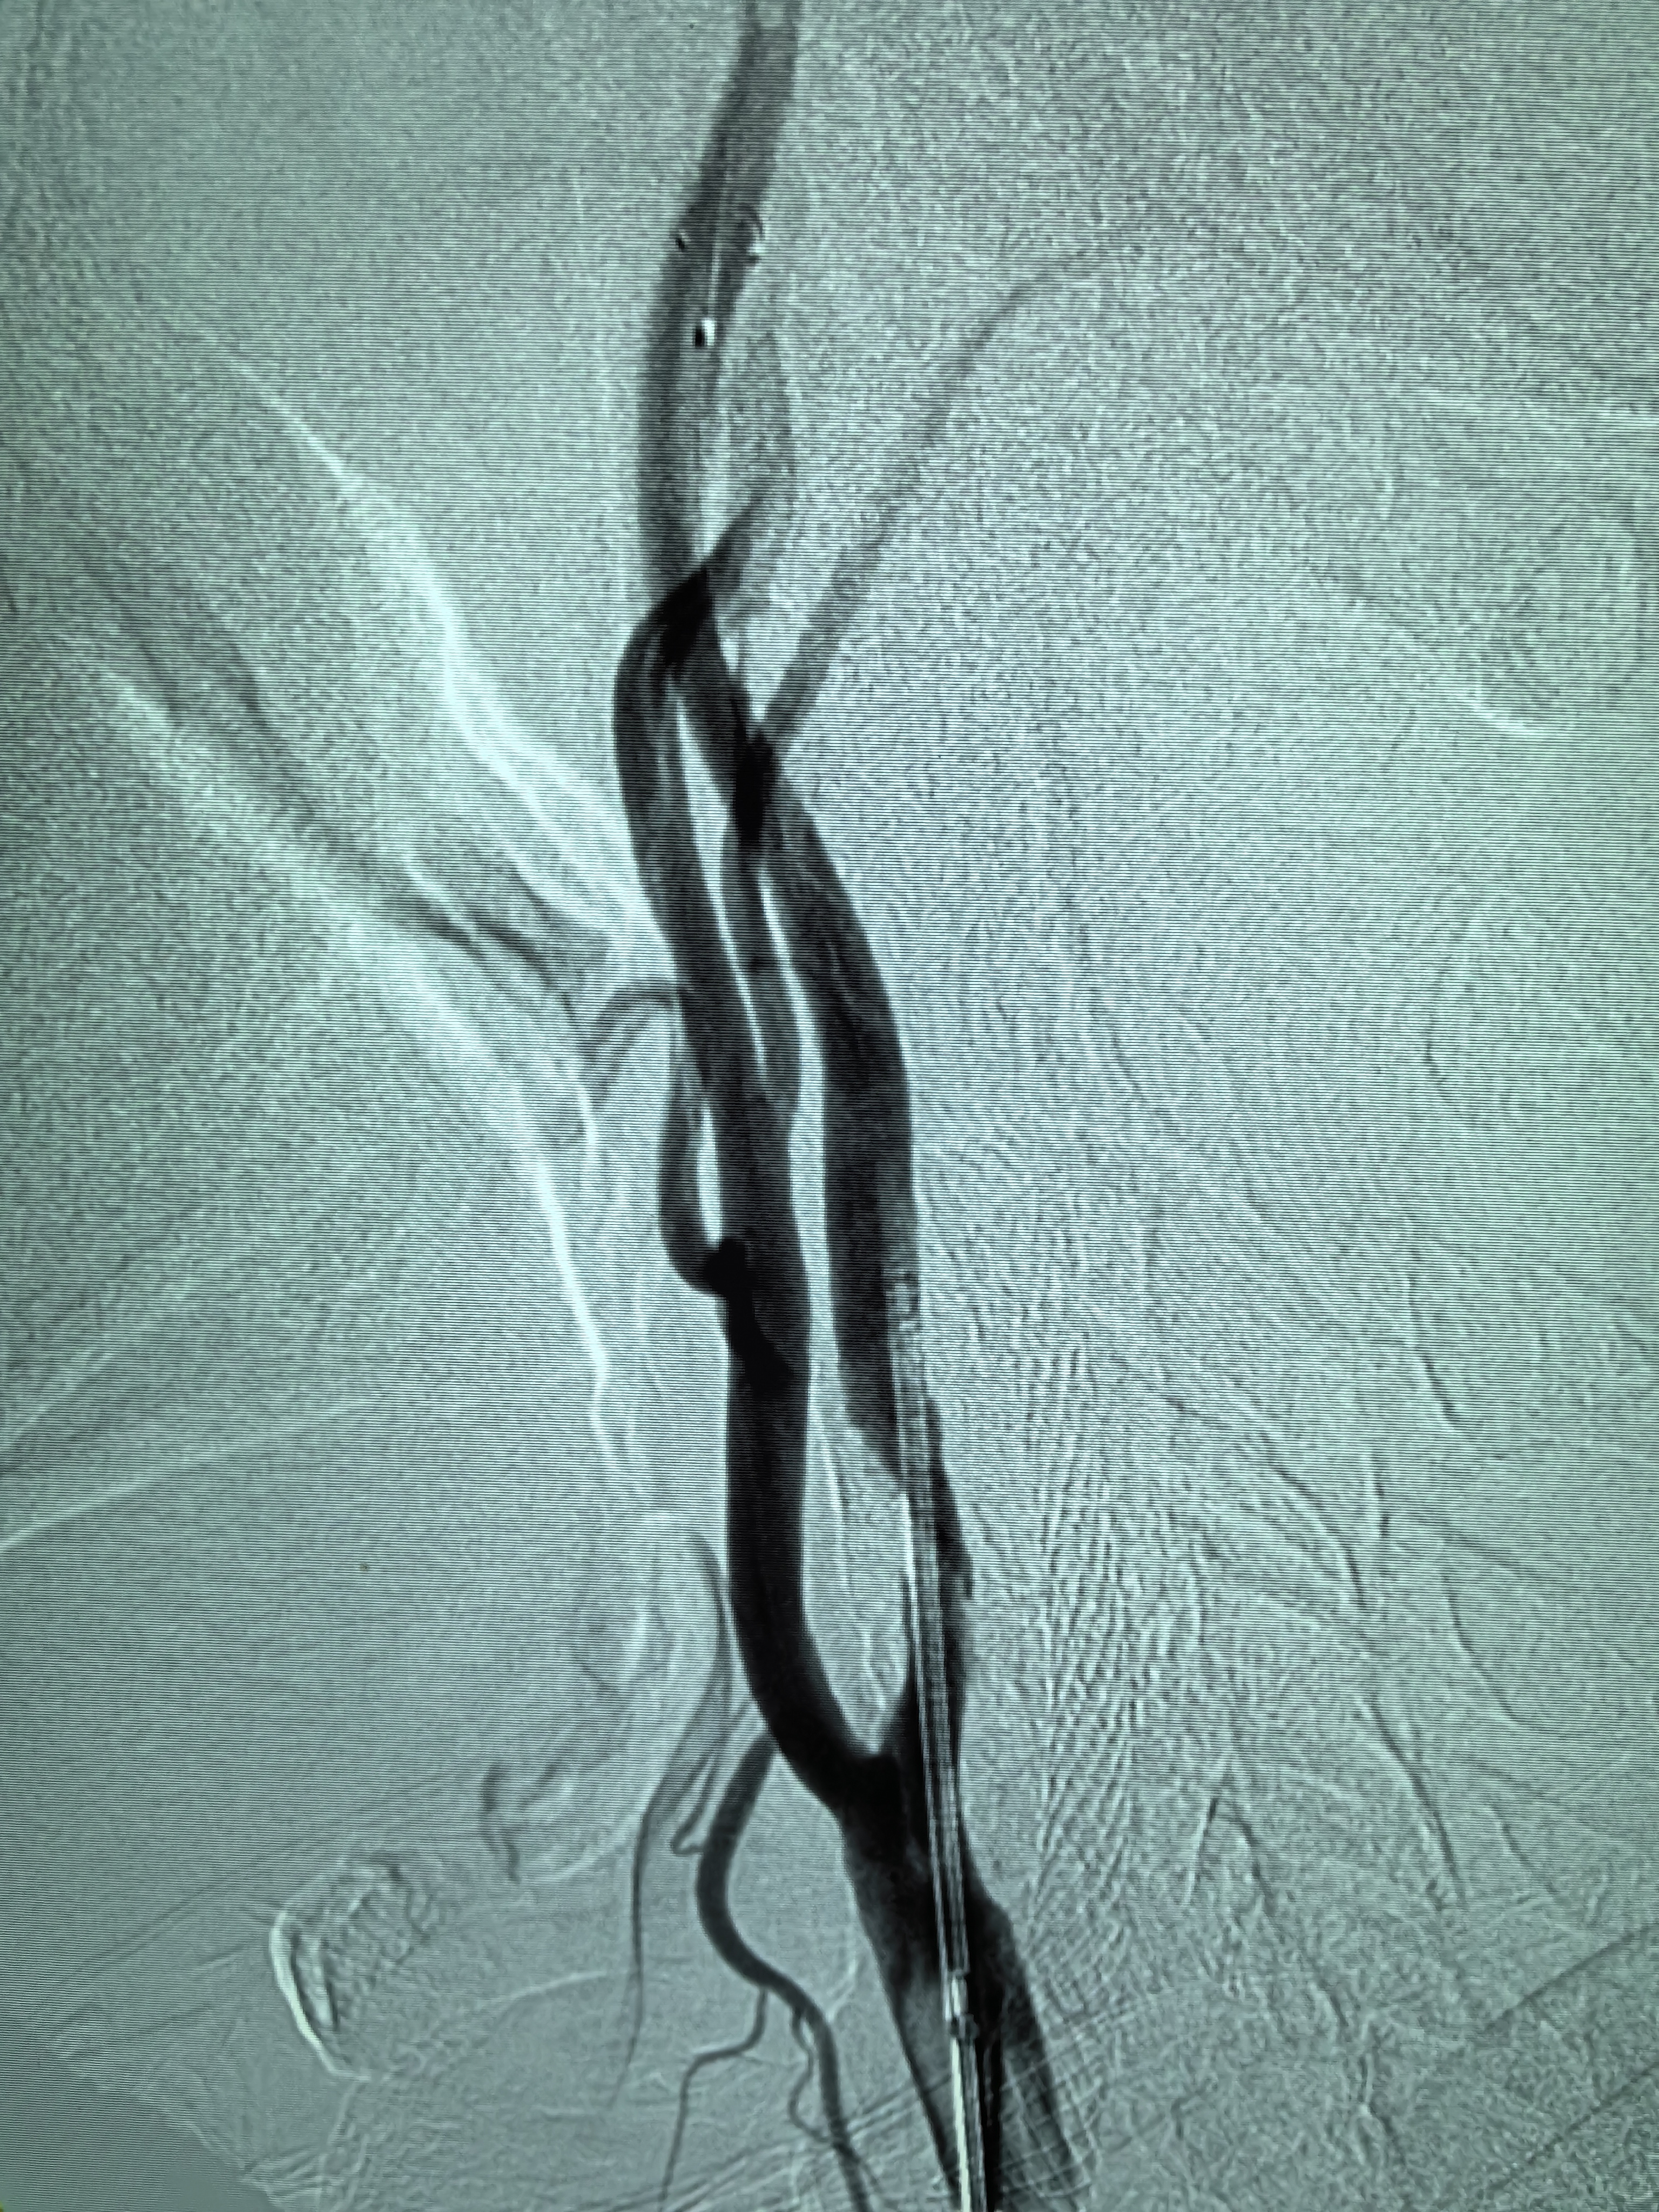

患者男性,70岁,体检发现双侧颈内动脉重度狭窄,1月前行右侧颈内动脉支架成形术,现为治疗左侧颈内动脉狭窄入院。既往高血压病史30年,口服硝苯地平控释片降压,血压控制130/80mmHg。

1、本例患者老年男性,双侧颈内动脉重度狭窄,治疗采取分期处理,间隔4周。

2、左侧颈内动脉从CTA看狭窄合并软斑,具备介入治疗指征。